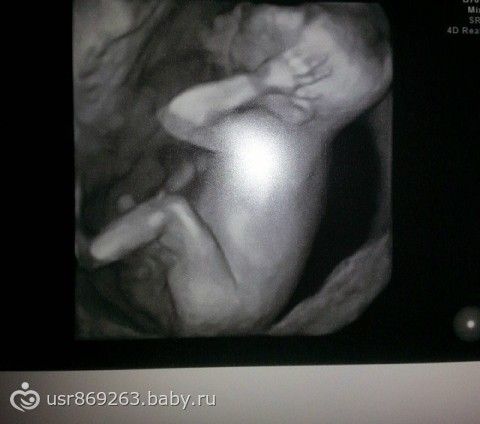

Мы в 17 недель весили 260 грамм!

Красивые! Где узи делали такое точное?

Это просто крупным планом но да мы большие

ничего себе! мы в 25 такие были

Я тоже думала мы будем по меньше но у нас плод большой и предлежание по передней стенке

Нам сказали у нас и плод не маленький

это ваше фото????